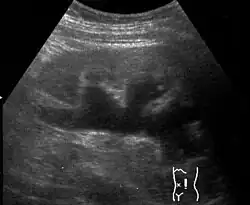

Renal ultrasonography of hydronephrosis caused by a left ureteral stone

Imaging studies, such as an intravenous urogram (IVU), renal ultrasonography, CT, or MRI, are also important investigations in determining the presence and/ or cause of hydronephrosis. Whilst ultrasound allows for visualisation of the ureters and kidneys (and determine the presence of hydronephrosis and / or hydroureter), an IVU is useful for assessing the anatomical location of the obstruction. Antegrade or retrograde pyelography will show similar findings to an IVU but offer a therapeutic option as well. Real-time ultrasounds and Doppler ultrasound tests in association with vascular resistance testing helps determine how a given obstruction is effecting urinary functionality in hydronephrotic patients.[12]